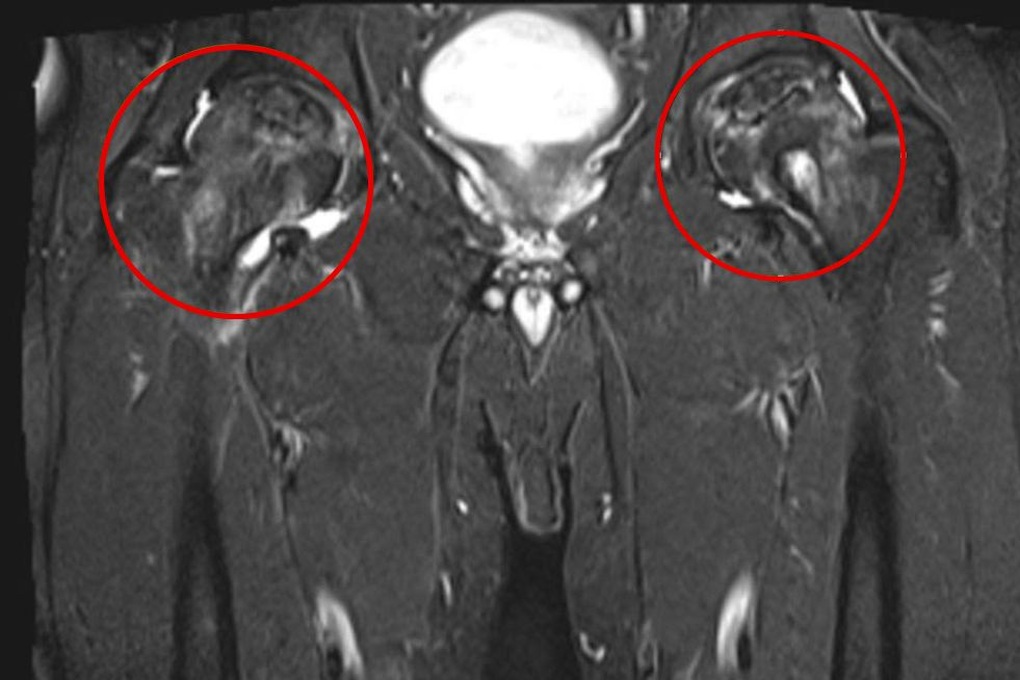

Hình ảnh khớp háng bị hoại tử của ông T (Ảnh: Bệnh viện).

Trường hợp bệnh nhân T phát hiện giai đoạn muộn là hiếm gặp, hình ảnh MRI cho thấy phần sụn khớp đã tổn thương độ III-IV không còn thích hợp để điều trị bảo tồn và khoan giảm áp, cần phải phẫu thuật thay khớp để cải thiện vận động.